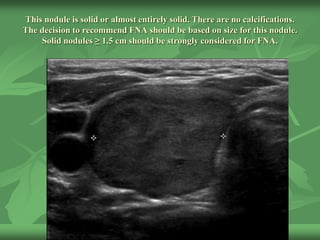

This nodule is solid or almost entirely solid. There are no calcifications.

The decision to recommend FNA should be based on size for this nodule.

Solid nodules ≥ 1.5 cm should be strongly considered for FNA.